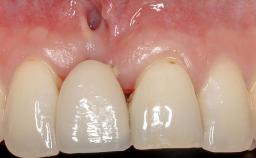

GBR and Soft-Tissue Augmentation Following Explantation to Rehabilitate a Soft- and Hard-Tissue Defect

It is sometimes necessary to remove and replace compromised implants. This case is a clear example of the need for multiple steps to achieve an optimal therapeutic result for patients with non-salvageable implants. It illustrates how the lost soft and hard tissues were rebuilt in a sequence that improved the healing of the hard tissues and assured their long-term stability. The 35-year-old healthy patient presented with clinical attachment loss on the proximal and lingual surfaces of the natural dentition. Some gingival recession was present on natural teeth, particularly in the posterior sextants (S1, S3, S4, and S6).

Prosthesis Type FDP